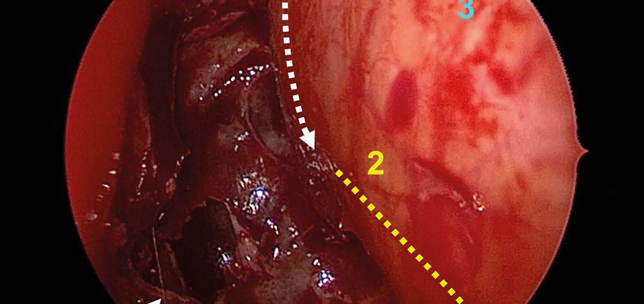

Current management of unilateral sporadic vestibular schwannoma

Vestibular schwannoma is the commonest tumour of the cerebellopontine angle (80%) and accounts for around 8% of all intracranial tumours. The commonest primary presenting symptoms are audio vestibular. Hearing health professionals are often the first contact for patients with potential symptoms of vestibular schwannoma, with the majority then being seen and diagnosed by otorhinolaryngologists.